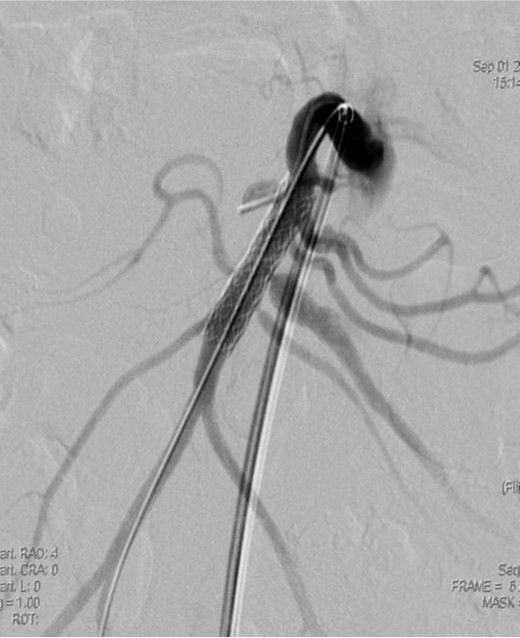

2009년 3월 복부 CT에서 SMA 기시부 하방 2cm 부위부터 5cm 길이의 편심성 혈전이 관찰되고 있으며 혈전이 있는 부위의 동맥 직경이 커져 있음(Fig. 1). 대동맥이나 분지 동맥에 동맥경화증의 소견은 관찰되지 않으며 심장초음파 및 심전도 검사에서 혈전이나 심방 세동은 없었음. CT 소견과 증상을 기준으로 spontaneous isolated SMA dissection으로 진단하였으며 창자의 허혈 소견이 보이지 않고 통증도 악화되지 않아 보존적 치료를 하였음. 2009년 6월 추적 CT에서 false lumen내 대부분의 혈전은 소실되었으나 SMA 기시부 5cm 하방 부위에는 국소적 혈전을 동반한 saccular pseudoaneurysm이 관찰됨. 2009년 8월 시행한 추적 CT에서 pseudoaneurysm의 직경이 2mm 증가함 (Fig. 2). 2009년 9월 시행한 혈관 조영술에서 saccular pseudoaneurysm이 SMA 기시부 5cm 하방부위에 관찰되며 SMA의 국소적 협착이 관찰됨 (Fig. 3). 스텐트와 코일을 이용한 혈관 내 치료 후 시행한 혈관 조영술에서 SMA의 국소적 협착과 pseudoaneurysm은 소실됨 (Fig. 4). 시술 3개 월 후 시행한 추적 CT에서 pseudoaneurysm은 완전히 소실되었으며 SMA는 정상소견을 보임(Fig. 5).

Fig. 3.

Fig. 3. Superior mesenteric angiography shows a saccular pseudoaneurysm with focal stenosis in the superior meseteric artery.